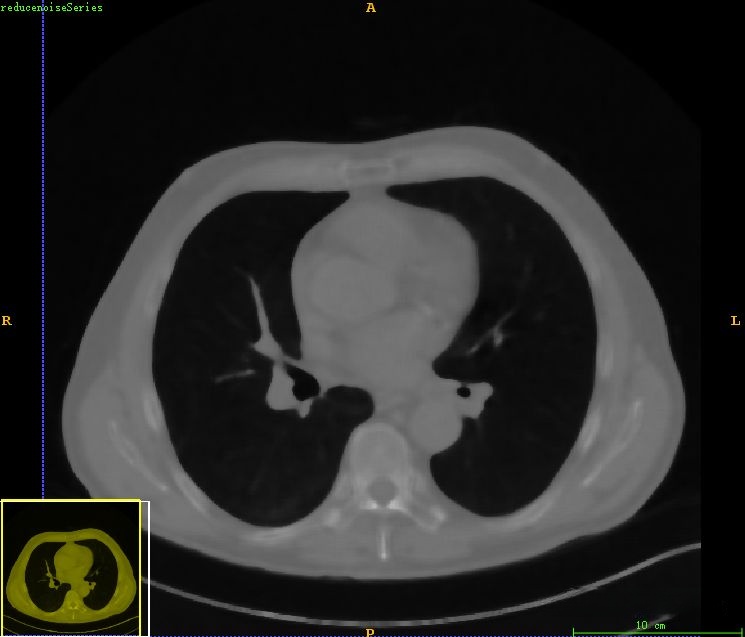

在原始CT图像中可见的是较大的噪声水平,在这种情况下会影响到后续的肺部分割过程。为此,在此阶段我们采用了中值滤波作为预处理手段以减少这一问题的影响。经过中值滤波处理后可以看出大部分噪声已被有效抑制然而这种现象并不会对我们后续的目标造成困扰因为我们的主要目标是提取出完整的肺部区域范围因此在这一操作完成后我们可以合理地忽略掉其中可能存在的残留干扰信息

最后得到肺部区域图像如下所示。